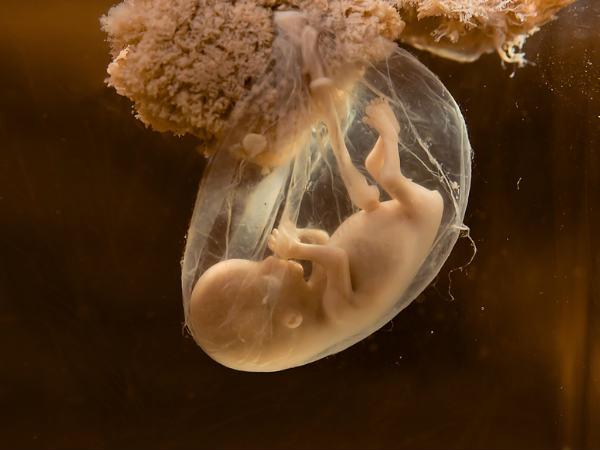

જાણો : ક્યારે પહેલી વાર ગર્ભમાં ભ્રૂણનું હૃદય ધબકે છે ?

જ્યારે અલ્ટ્રાસાઉંડનાં મૉનિટર પર બાળકનું હૃદય દેખાય છે અને ધબકારા ચાલતા રહે છે, પરંતુ એવી ઘણી બધી બાબતો ઝે કે જેની આપ કલ્પના પણ નથી કરી શકતાં.

આપ બાળકને જન્મ આપવાનાં હોવ, ત્યારે મોટાભાગની મહિલાઓ માટે માતૃત્વનો આ અહેસાસ પહેલી વખત અલ્ટ્રા સાઉંડ સાથે થાય છે.

ભ્રૂણની હાર્ટબીટ, પ્રેગ્નંસી, જન્મ અને બાદમાં આપનાં બાળકનાં આરોગ્યમાં મહત્વની ભૂમિકા ભજવે છે. એ સારી વાત છે કે આપનાં બાળકનાં હૃદયનાં ધબકારાને જોવાની ટેક્નિક ઘણી માહિતીઓ પ્રદાન કરે છે. સગર્ભાવસ્થા દરમિયાન બધુ બરાબર રહે અને જન્મજાત હૃદયની બીમારીઓનું વહેલી તકે જાણ થઈ જાય છે.

બાળકનું હૃદય :

શરુઆતમાં એક ટ્યૂબની સંરચના થાય છે કે જે એક ચૅમ્બર્ડ અંગમાં વિકસિત થાય છે કે જેનાથી આપણે વાકેફ છીએ. નિષેચનનાં થોડાક દિવસો બાદ તે વિકસિત થઈ જાય છે. અમે આપને આ અંગે કેટલીક માહિતી પ્રદાન કરી રહ્યાં છીએ.

ત્રીજુ અઠવાડિયુ : નિષેચનનાં 22 દિવસ બાદ ભ્રૂણનું હૃદય બનવાનું શરૂ થાય છે, પરંતુ તેના ધબકારા નથી સંભળાતા

પાંચમુ અઠવાડિયુ : ભ્રૂણનું હાર્ટ ચૅમ્બર વિકસિત થવાનું શરૂ થાય છે.

બાળકનું હદય :

છઠ્ઠુ અઠવાડિયુ : હાર્ટ રેટ 100-160 બીટ્સ પર મિનિટ (બીપીએમ) થઈ જાય છે. આ સમય આપ અલ્ટ્રાસાઉંડ મૉનિટર પર ધબકારા જોઈ શકો છો.

આઠમુ અઠવાડિયુ : હાર્ટ રેટ 170 બીપીએમ સુધી વધી જાય છે અને જન્મનાં સમયે 130 બીપીએમ પર લગભગ સ્થિર થઈ જાય છે.